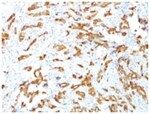

HSP27 Monoclonal specifically detects HSP27 in Human, Mouse, Rat, Chicken, Chimpanzee, Monkey, Sheep samples. It is validated for Western Blot, Flow Cytometry, Immunohistochemistry, Immunocytochemistry/Immunofluorescence, Immunohistochemistry-Paraffin.Specifications

| This MAb reacts specifically with heat shock protein HSP27 in human and monkey tissues and cell lines such as MCF-7. HSP27, also referred to as the Estrogen-Regulated 24K protein and HSP28, is one of several small heat shock proteins produced by all organisms studied. HSP27 synthesis is induced by elevated temperature, as well as by estrogen in hormone responsive cells. Interestingly, human HSP27 also shares greater than 50% homology with low molecular weight Drosophila HSPs and mammalian alpha-crystalline lens protein. Because of the estrogen responsive nature of HSP27, this protein has been studied extensively in human estrogen responsive tissues such as cervix, endometrium and breast tissue. Therefore HSP27 may be useful in classifying various hormone sensitive tumors. |